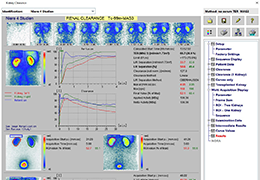

ANYTHINK 经导管主动脉瓣膜置换术分析系统